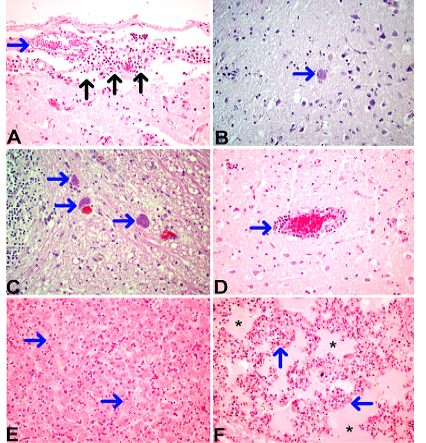

Figure 3

Necropsy findings